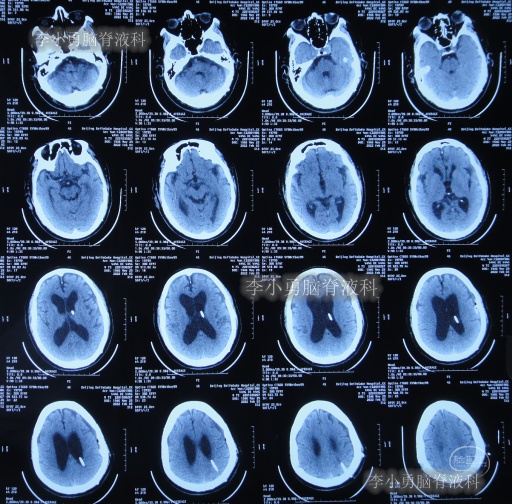

2020年10月29日(发病已8年),因症状一直没有得到改善且呈进行性加重趋势,查头部核磁示脑积水(图-1)。

图-1:2020年10月29日头部核磁